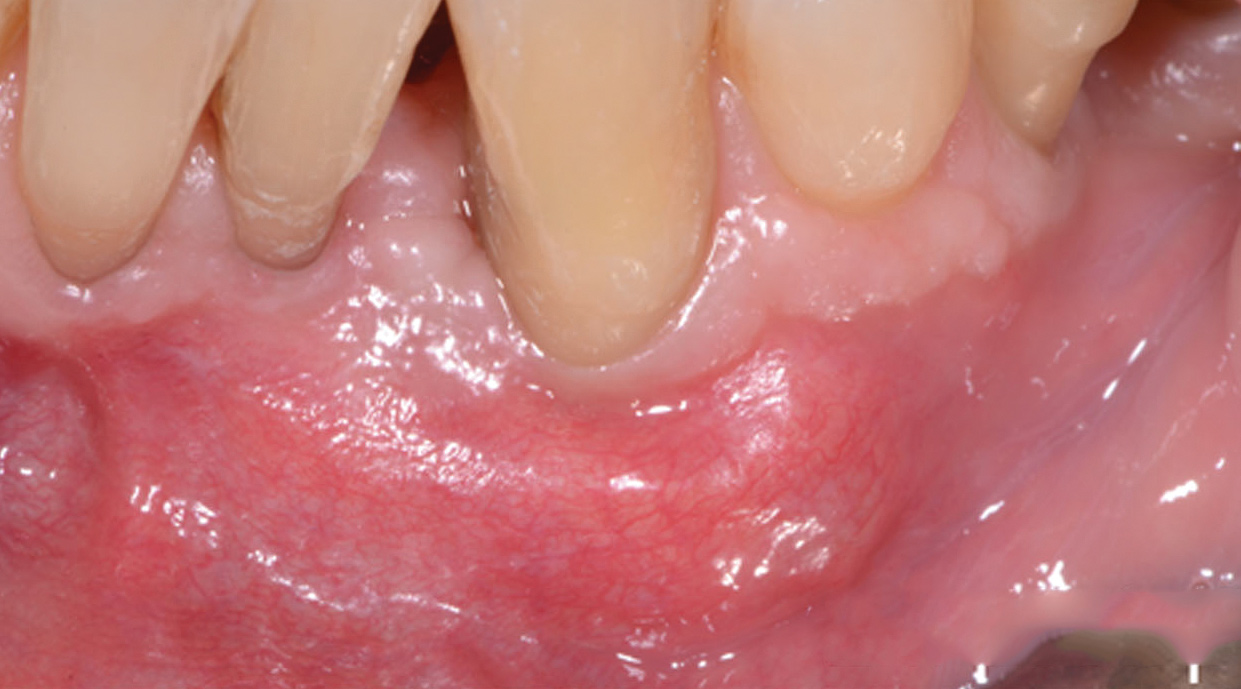

Fig 13. The scaffold was placed in the defect, where it remained for approximately 1 year. Fig 13: baseline; Fig 14: defect; Fig 15: scaffold matrix; Fig 16: scaffold placement; Fig 17: wound closure; Fig 18 through Fig 20: 2-month, 6-month, and 1-year postoperative, respectively. (Images reprinted with permission from Rasperini G, Pilipchuk SP, Flanagan CL, et al. J Dent Res. 2015;94[9 suppl]:153S-157S.)

Figure 13

Fig 14. The scaffold was placed in the defect, where it remained for approximately 1 year. Fig 13: baseline; Fig 14: defect; Fig 15: scaffold matrix; Fig 16: scaffold placement; Fig 17: wound closure; Fig 18 through Fig 20: 2-month, 6-month, and 1-year postoperative, respectively. (Images reprinted with permission from Rasperini G, Pilipchuk SP, Flanagan CL, et al. J Dent Res. 2015;94[9 suppl]:153S-157S.)